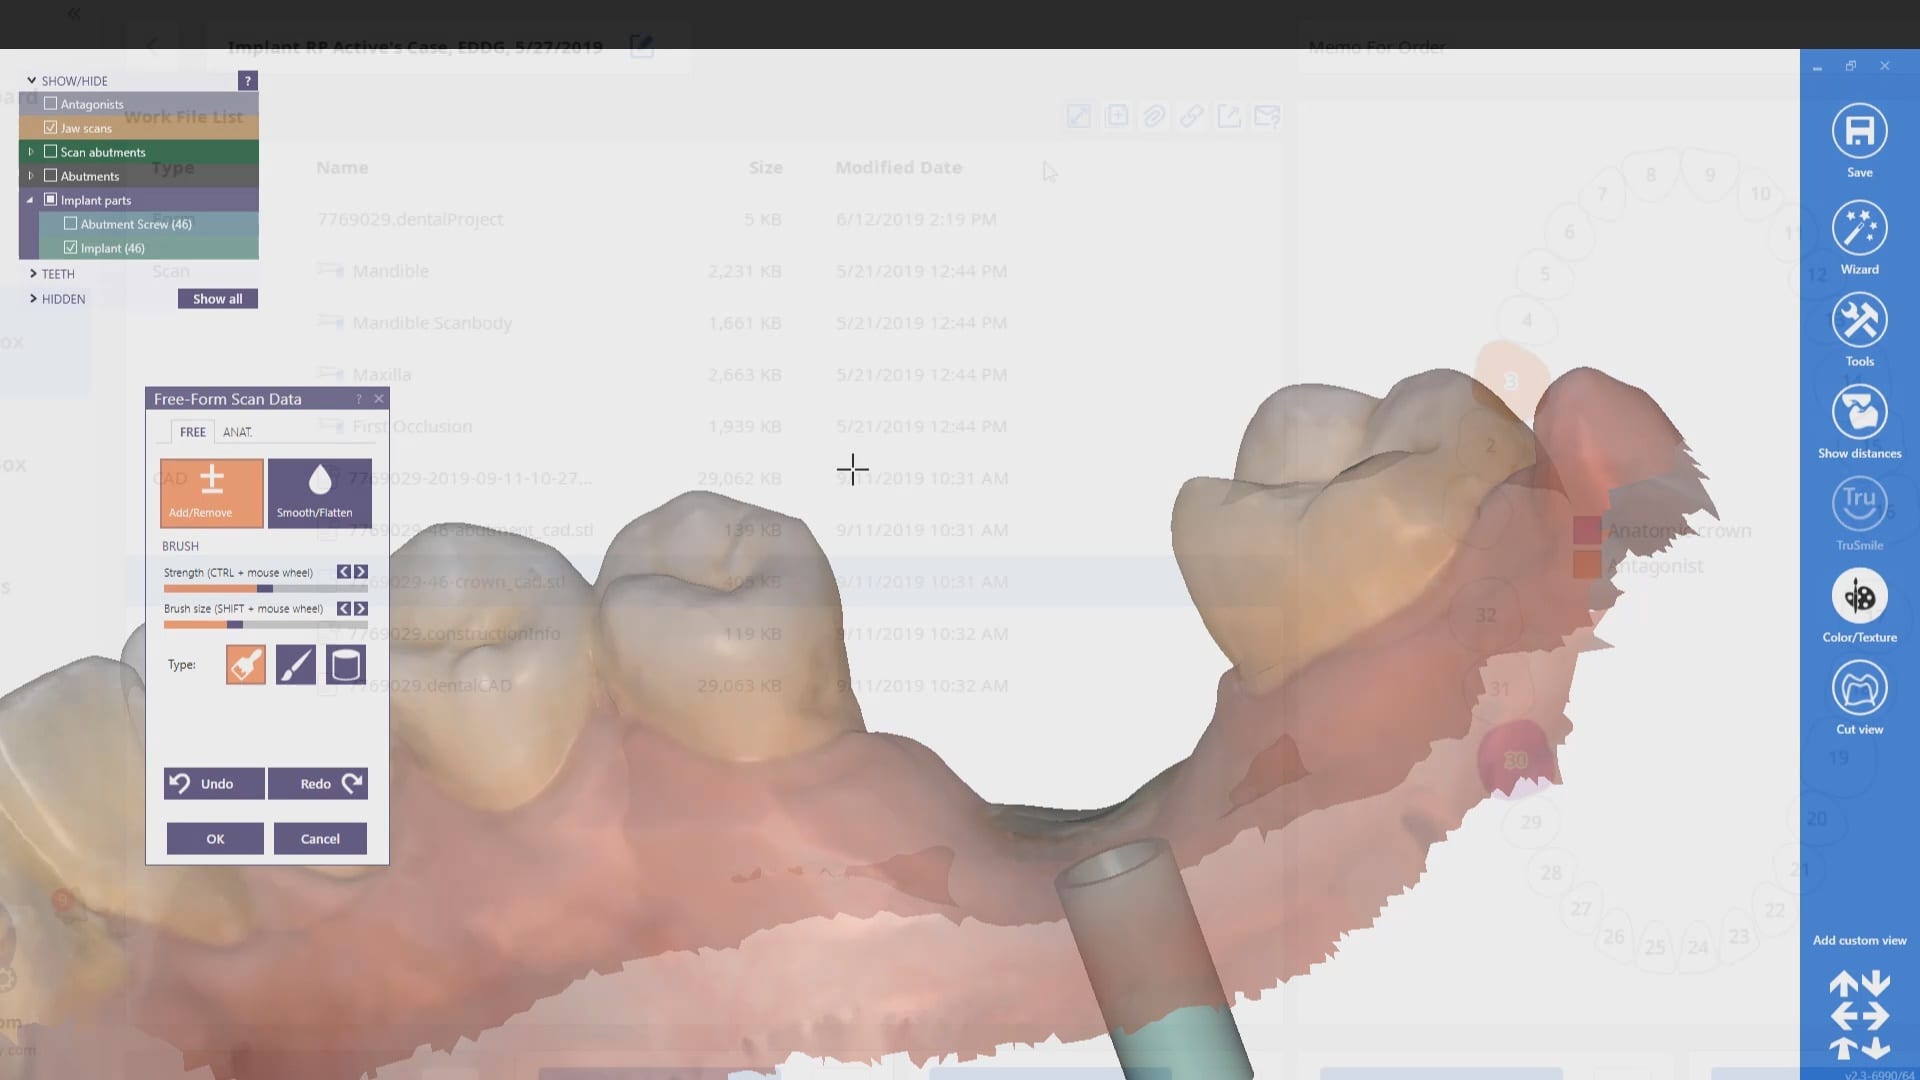

In this article we demonstrate how two separate implants are placed with guided surgery and then scanbodies are used immediately after placement to capture the location of the fixtures. While […]